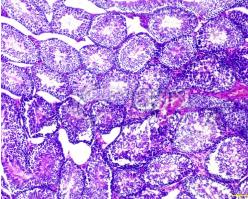

组织切片伴随着显微镜技术和免疫实验等的发展而得到广泛的应用。本文对其中的冰冻切片、石蜡切片、碳蜡切片、超薄切片、塑料切片等几种常用的实验方法相关操作步骤进行介绍。

石蜡切片

其优点是组织结构保存良好,在病理和回顾性研究中有较大的实用价值,能切连续薄片,组织结构清晰,抗原定位准确。用于免疫组化技术的石蜡切片制备与常规制片略有不同:①脱水、透明等过程应在4℃。C下进行,以尽量减少组织抗原的损失。②组织块大小应限于2cm×1.5cm×0.2cm,使组织充分脱水、透明、浸蜡。③浸蜡、包埋过程中,石蜡应保持在60℃以下,以溶点低的软蜡最好(即低温石蜡包埋)。

石蜡切片为常规制片技术,切片机多为轮转式,切片厚度2~7μm,应用范围广,不影响抗体的穿透性,染色均匀一致。由于甲醛固定、有机熔剂和包埋剂对组抗原有一定的损害及遮蔽,使抗原特征发生改变。有人报告经蛋白酶消化,可以改善光镜免疫组化染色强度,常用的有胰蛋白酶、链霉蛋白酶及胃蛋白酶等消化法。石蜡切片应入37℃恒温箱过夜,这样烤片可减少染色中脱片现象。切片如需长期贮存,可存放于4℃冰箱内备用。